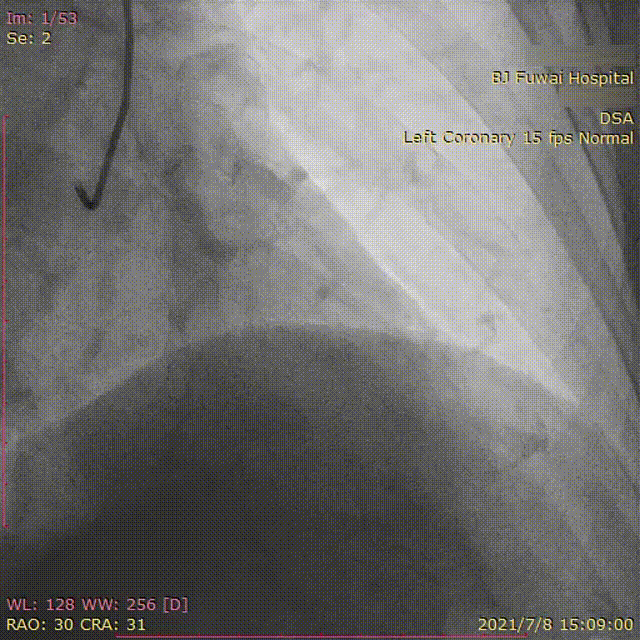

冠脉造影:

提示LAD中段临界局限病变(图1),LCX主支尚可,分支重度病变(图2),RCA近段闭塞,逆向造影发现RCA较小(图3、图4)。

图3.RCA